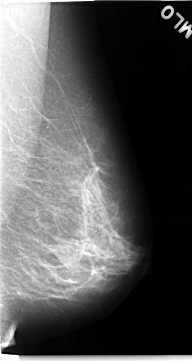

C_0068_1.LEFT_MLO

LEFT_MLO LINES 4688 PIXELS_PER_LINE 2496 BITS_PER_PIXEL 12 RESOLUTION 50 NON_OVERLAY